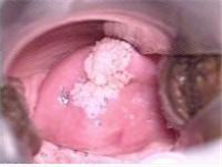

非特异性外阴炎

女性外阴受一般细菌(如葡萄球菌、大肠杆菌、链球菌)、粪便、阴道分泌物或其他物理化...